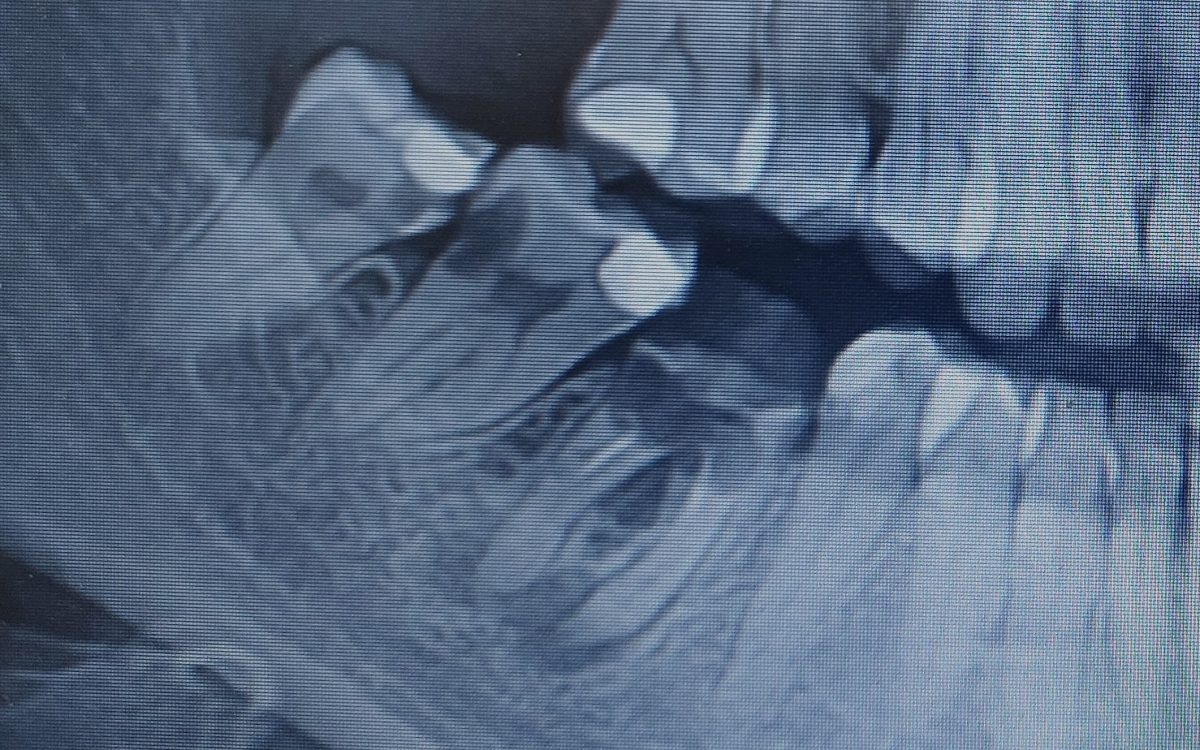

Az állapotfelmérés során átvizsgáljuk a fogat, a fogínyt, majd a még pontosabb diagnózishoz digitális panoráma röntgenfelvételt készítünk és ezek alapján összeállítjuk a szükséges feladatokat, amikről kezelési tervet is készítünk. A panoráma röntgenfelvétel segít abban, hogy a fogak és az íny szabad szemmel nem látható részén az esetleges gyulladást vagy egyéb eltéréseket felfedezzük.

Sokszor olyan szuvasodások indulnak el a fogban, amelyet magunkon a tükörben, szabad szemmel nem látunk. A fog száj felöli oldalán, a szomszédos fog mellett is megbújhatnak a káros baktériumok, melyek szorgalmasan károsítják a fogat, egyre mélyebbre hatolva. Eközben pedig nem okoznak fájdalmat, érzékenységet. Ezeket gyakran csak állapotfelméréskor a röntgenfelvétel segítségével találhatjuk meg.

- Milyen állapotban van eredetileg a fog (pl. szuvas-e, szükséges-e gyökérkezelés, van-e fogágygyulladás)? Ezért első körben egy röntgenfelvételt szoktunk készíteni, hogy a fog szabad szemmel nem látható részeit és környezetét is felmérhessük.

Az adott fog eltávolítása mindig előzetes vizsgálatot követően történik, ahol röntgenfelvételen is meggyőződünk arról, hogy a fog valóban menthetetlen.

- Konzultáció, amihez CBCT felvétel szükséges az implantátum(ok) pontos helyének beméréséhez

A bölcsességfognak nem kell szuvasnak, tömöttnek vagy töröttnek lennie ahhoz, hogy komoly fájdalmat vagy problémát okozzon. A legtöbb esetben maguk a fogak teljesen egészségesek, azonban az állcsontban nincsen elegendő hely számukra, ferdén fejlődnek, így torlódást, szuvasodást idézhetnek elő a szomszédos fogakon, vagy feszítést, gyulladást, csont felszívódást váltanak ki a környező szövetekben. A fentiek miatt legtöbbször a környező szövetek, fogak megóvása érdekében van szükség arra, hogy eltávolítsuk őket.

- Amennyiben eltávolítása sokkal nagyobb rizikóval jár, mint megtartása és panaszmentes(mindenképpen röntgen vagy CT felvétel szükséges ennek megítéléséhez)